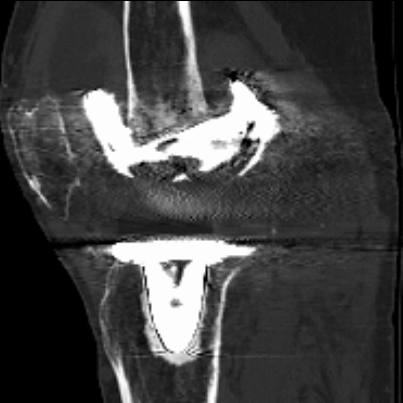

▲CT提示:假体松动,

内侧股骨髁、内侧胫骨平台骨缺损严重